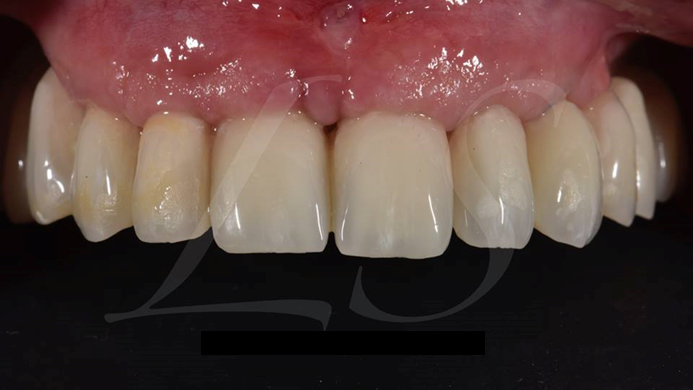

Clinical case: AnyRidge immediate loading

- Courtesy of Dr. Andres Paraud Freixas, Chile -

AnyRidge, ISQ value, initial stability, immediate loading, KnifeThread, maxillary anterior, Mega ISQ, Dr. Andres Paraud Freixas

AnyRidge implant system, Mega ISQ, Digital prosthesis

“Patient’s smile was recovered on the day of surgery

with reliable & highly-aesthetic results using AnyRidge & R2GATE. ”